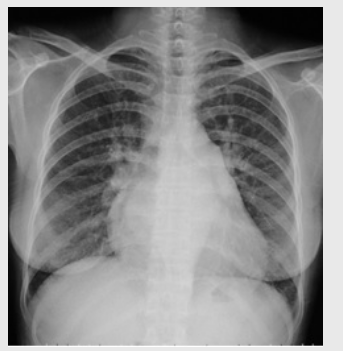

01卷-4.根據下圖請做出正確診斷

A.右側肺炎

B.兩下肺炎

C.右下肺肺癌

D.正常胸片

正確答案:B/D/C/A/A/D/D/D